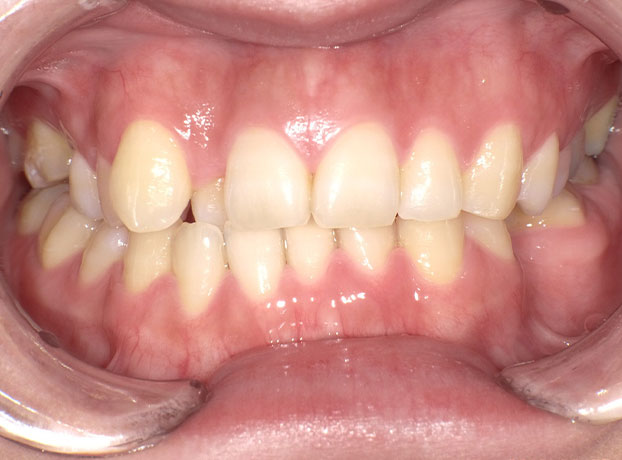

◆ワイヤー矯正(30代女性)

(主訴)歯並びを良くしたい。

右上前歯以外にも奥歯の噛み合わせも改善した方が良かったため、歯の表にワイヤーを装着する、オーソドックスな方法にて矯正。

審美面も機能回復の面でも矯正治療により改善する事が出来た。